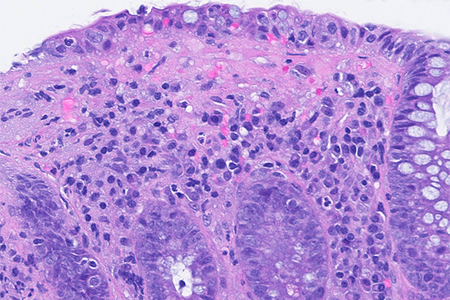

Colon biopsies in a 87 year-old female with chronic watery diarrhea.

Collagenous colitis with giant cells.

An 87-year-old woman presented with chronic, non-bloody, watery diarrhea and underwent colonoscopy, which revealed no endoscopic abnormalities. Biopsies were taken.

Histology of several colonic sites showed a thickened subepithelial collagen band (>10 μm), predominantly beneath the superficial epithelium but also surrounding the crypts (Panel A). Surface epithelial injury was also observed, with focal mucin depletion and detachment of superficial epithelial cells (Panel B). Lamina propria showed increased cellularity, with lymphocytic and plasmocytic infiltration, along with numerous giant cells (Panel C). There was no crypt architectural distortion. The collagen deposition was highlighted by Masson’s trichrome stain (Panel D) and strongly by tenascin immunohistochemistry (Panel E).